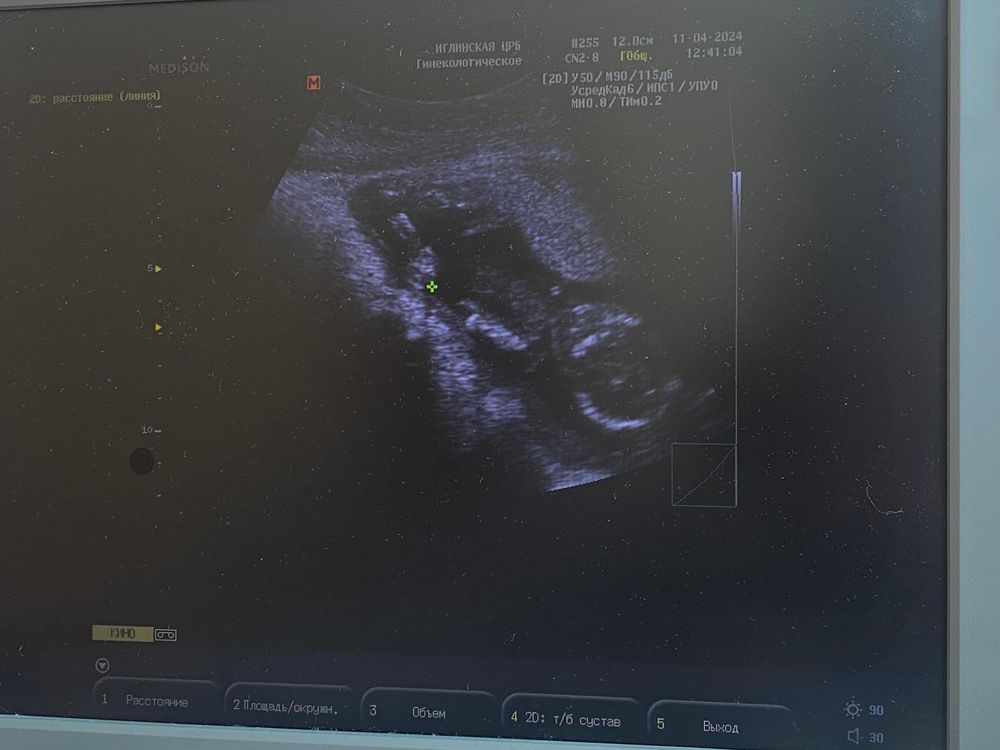

УЗИ 16 недель

На узи сказали , что малыш на сроке 16 нед. и 2 дня. Подтвердили пол - у нас будет мальчик 👶🏼

Дали сфотографировать, хоть аппарат и не новый , но хоть как то🥰

справа снизу голова, на нас смотрит, попа наверху 🙂